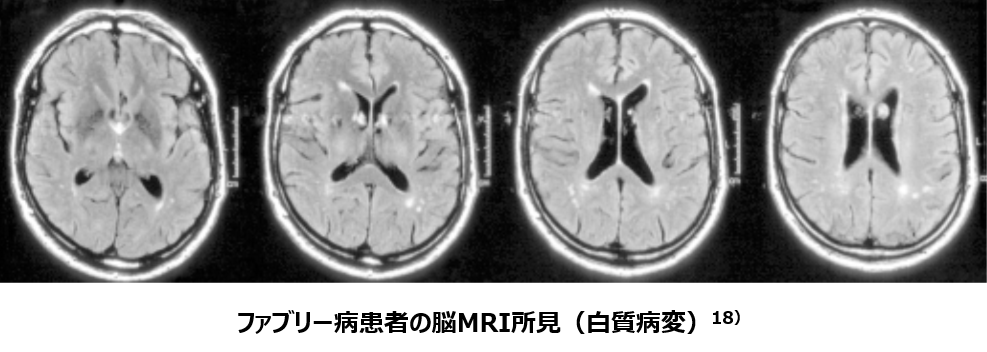

脳血管障害

・ファブリー病患者の16%ほどが何らかの脳⾎管障害を合併することが知られています16)。

・Fabry Registry(ファブリー病の国際市販後調査)では、男性患者の6.9%に、⼥性患者の4.3%に観察されています16) 。

・脳⾎管障害は、GL-3が⾎管内⽪細胞のライソゾームに集積し、細胞が膨化することにより⼩細動脈に狭窄が⽣じることで起こります17) 。

・優位に拡張した椎⾻・脳底動脈はファブリー病で特徴的であることが報告されました17)。

18)Ginsberg_Pract Neurol 2005,5,110-113